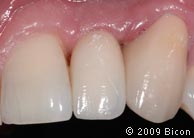

70. Снимок сделан через два месяца после установки.

71. Интегрированные коронки (IAC)